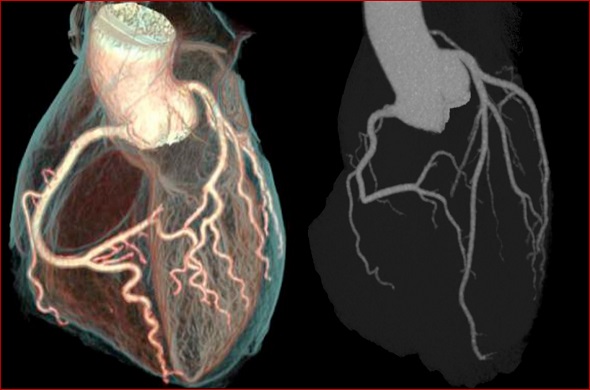

INSUFFICIENZA CORONARICA

“Il cuore è debole. Un vaso chiamato “il ricevente” è quello che lo provoca. È questo vaso che dà acqua al cuore” (Ebers 855c). Il vaso che fornisce “acqua” sembrerebbe riferito alle coronarie, che per un’occlusione non forniscono più nutrimento al muscolo cardiaco.

“La debolezza è sorta nel suo cuore. Ciò significa che si inarca fino ai confini del polmone e del fegato. Lì accade che i suoi vasi diventino sordi, caduti a causa del loro calore” (Ebers 855d). L’immagine del cuore che si estende oltre il normale richiama immediatamente la cardiomiopatia dilatativa, quando la cavità cardiaca si allarga per la perdita di forza di contrazione del muscolo cardiaco, riducendo così in maniera sensibile la capacità che ha il cuore di pompare il sangue (“i vasi diventano sordi”, ossia non pulsano più).

In questa immagine però altri studiosi hanno individuato i sintomi degli aneurismi aortici

“(il cuore) si inarca fino ai confini del polmone e del fegato. Lì accade che i suoi vasi diventino sordi…” L’ingrossamento del cuore ma con l’assottigliamento delle pareti del ventricolo sinistro nella cardiomiopatia dilatativa